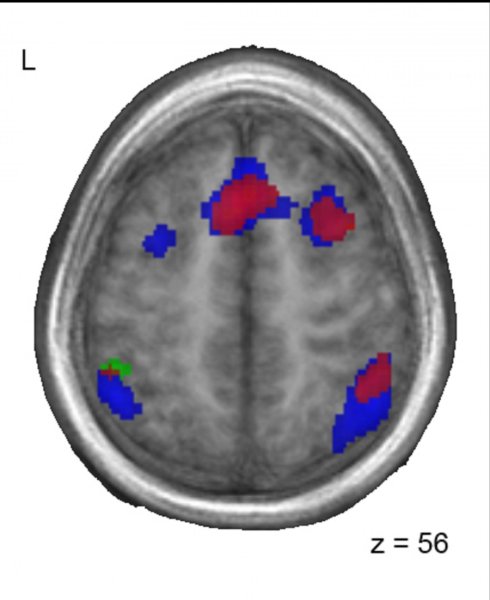

Patrones similares de actividad cerebral entre los bilingües chino-francés (rojo) y los adoptados (azul) cuando realizan una tarea con sonidos de francés. Imagen: Lara Pierce. Fuente: Universidad McGill.

Aunque todos los grupos realizaron las tareas igual de bien, las áreas del cerebro que se activaban difirieron entre los grupos. En los niños franceses monolingües sin exposición a China, se activaron las áreas del cerebro que se esperaba que intervinieran en el procesamiento de los sonidos del lenguaje, especialmente el giro frontal inferior izquierdo y la ínsula anterior. Sin embargo, entre los niños que eran bilingües (chino / francés) y los que habían sido expuestos al chino de pequeños y luego habían dejado de hablarlo, se activaron además otras áreas del cerebro, particularmente la circunvolución frontal media derecha, la corteza frontal medial izquierda, y el giro temporal superior bilateral.

Los investigadores observaron que los niños chinos que habían sido adoptados por familias francesas monolingües y ya no hablaban chino, y por tanto eran funcionalmente monolingües en el momento de la prueba, todavía tenían cerebros que procesaban el lenguaje de una manera similar a los niños bilingües.